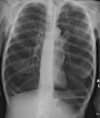

Neumonía bacteriana (radioopacidad)

62

Neumonía lobar (usualmente por S. pneumoniae)